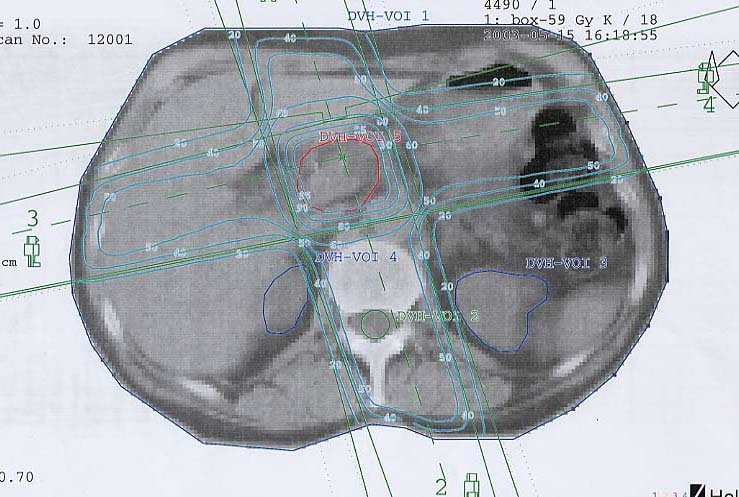

Tumore der Bauchspeicheldrüse (Pankreas): Bestrahlungsplan